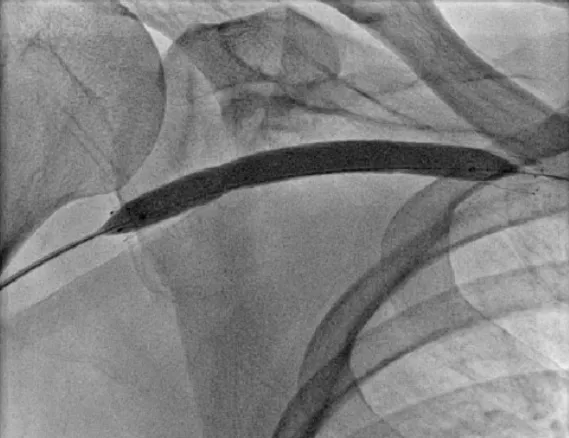

Lockterapia no Tratamento de Infecções de Cateter de Hemodiálise

A lockterapia é uma ferramenta essencial na prática nefrológica, permitindo o controle eficaz das infecções de cateter sem comprometer a funcionalidade do acesso vascular. A adoção de protocolos baseados em evidências, conforme as diretrizes da KDOQI 2019, é fundamental para otimizar o manejo das infecções associadas ao CVC, minimizando complicações e melhorando o prognóstico dos pacientes dialíticos.